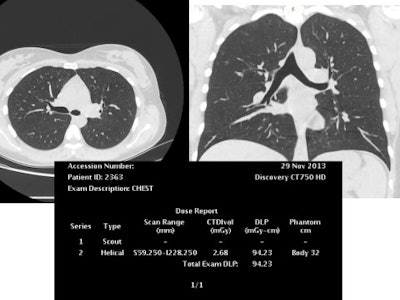

The new study comprises retrospective analysis performed using data from electronic patient records and PACS in the 450-bed Federal Center of Medicine and Rehabilitation in Moscow. Results were obtained for 1,626 patients (794 men, 832 women; age range 17 to 93) scanned during one year with one 40-slice and two 64-slice scanners. Volumetric CT dose index (CTDI) and dose-length product (DLP) were collected for each examination. The main findings can be seen in the tables below.

First presented at ECR 2015 by Dr. Elena Matkevich et al, the study showed the total number and structure of exams in a selected federal hospital between 2012 and 2013. Published as a paper in Russian in the journal Vestnik rentgenologii i radiologii (January-February 2016, Vol. 97:1, pp. 41-47), and with additional data, the study shows the structure and number of CT between 2012 and 2014. Both poster and paper also analyzed radiation exposure from CT per anatomical area and by scanner setting, and illustrated the feasibility of routine low-dose CT without the loss of diagnostic capacity.

The distribution of CT examinations according to anatomical regions scanned was as follows: brain (n = 329), chest (596), abdomen-pelvis (529), and chest-abdomen-pelvis (172). Data on the scanning parameters of each study were also collected and the mean CTDI and DLP were defined. Effective dose was calculated using the normalized coefficients according to the International Commission on Radiological Protection (ICRP) guidelines.

In the final part of the study, Matkevich et al analyzed the image quality of low-dose CT examinations of the heart and coronaries, chest, and carotids. According to the authors, good diagnostic quality was maintained despite a reduction in radiation exposure, this achieved with decreased tube voltage (80 kV to 100 kV) and tube current in combination with iterative reconstruction (ASIR and MBIR).

This reconstructed noncontrast CT image of the chest (lungs) was also achieved with reduced tube voltage of 80 kVp and automatic tube current modulation.A great enthusiast for iterative image reconstruction, he believes such techniques spell change for overall radiation reduction to patients and the wider population. However, he is aware that even when such tools are available, some doctors continue to choose standard protocols on advanced CT machines when low-dose protocols would be feasible.